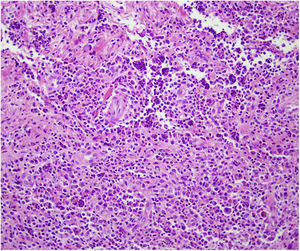

HistopatologíaEl estudio histopatológico mostró una epidermis de apariencia normal que asentaba sobre una dermis ocupada en su totalidad por un infiltrado inflamatorio formado por histiocitos espumosos, células plasmáticas, fibroblastos y abundantes neutrófilos (fig. 2). Las tinciones para PAS, GRAM, Giemsa y Grocott no evidenciaron microorganismos patógenos.

El diagnóstico diferencial se plantea en primer lugar con infecciones cutáneas por micobacterias u hongos, en cuyo caso las tinciones con PAS y Grocott, así como los cultivos, mostrarían resultados positivos. En segundo lugar, con tumores cutáneos, principalmente del grupo de los linfomas; en este caso los hallazgos histopatológicos serían determinantes.